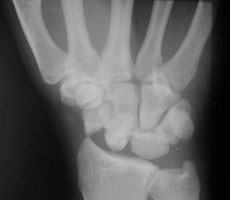

- Click on the image for a larger versionBLateral radiograph of the wrist. This shows the normal relationship of the lunate relative to the radius but there is dorsal displacement of the capitate bone.

The perilunate dislocation results from a backwards fall on an extended hand which disrupts the scaphoid ligaments. The capitate is dorsally located relative to the lunate. The lunate bone maintains its normal relationship with the radius.